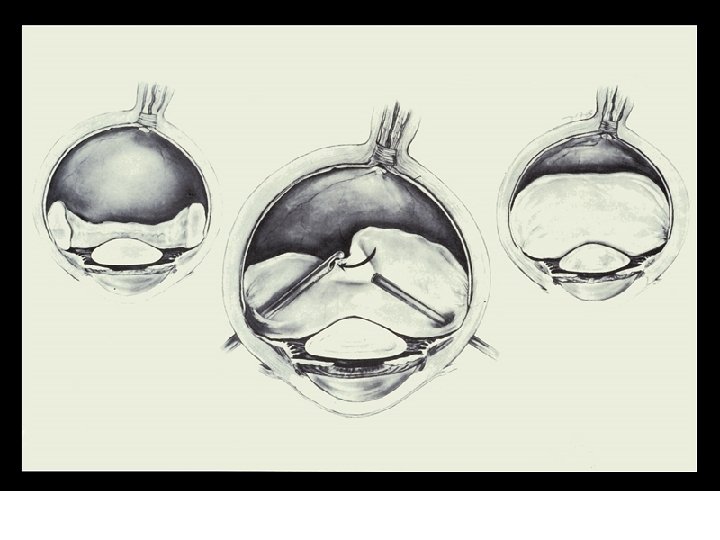

VII. PATHOLOGY AND AGE RELATED CHANGES z. C. Vitrectomy y 1. this surgical procedure was not performed until the 1970's y 2. incision made in pars plana y 3. micro-surgical instrument inserted xa. takes up a small piece of vitreous, cuts it, removes it and then replaces with an equal volume of saline